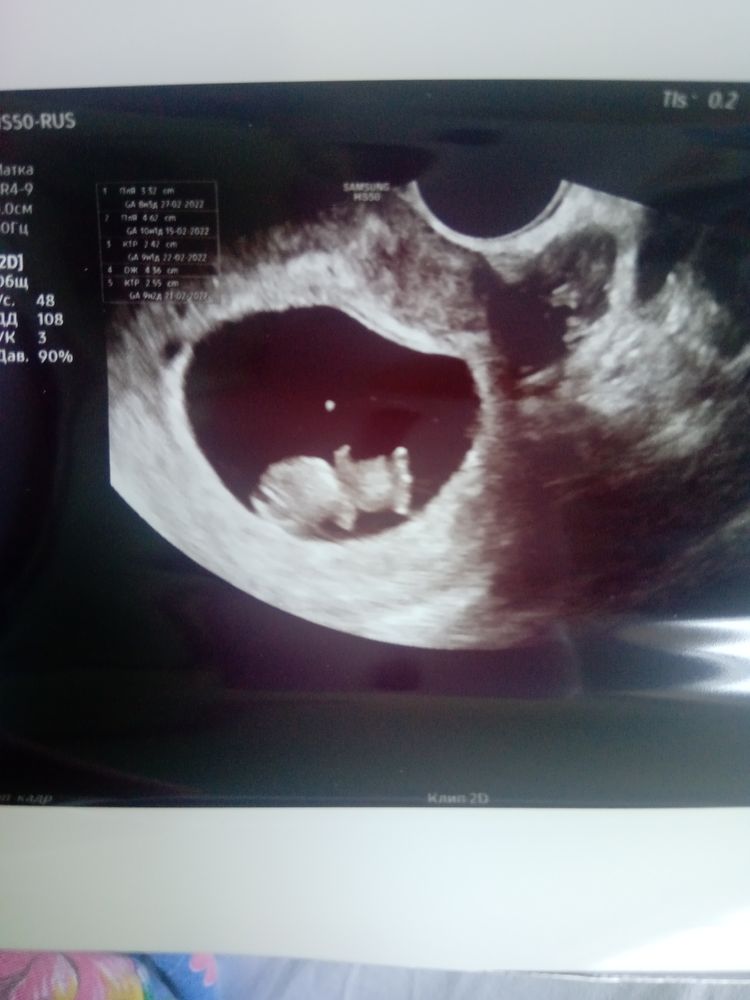

Узи 9 недель